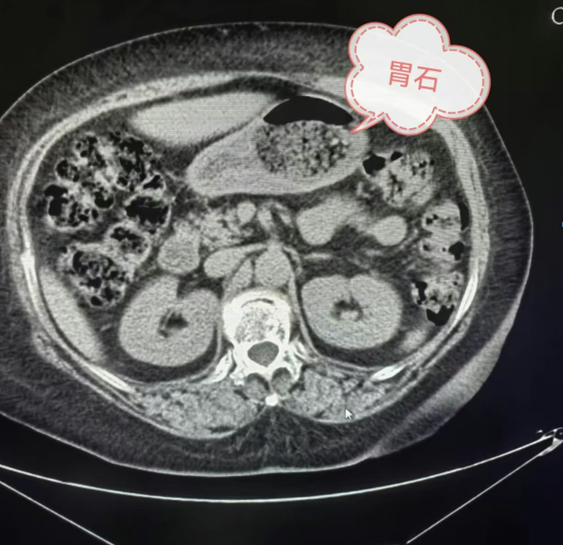

四、CT影像:胃结石的“个性画像”

在胃结石的 CT 影像中,不同类型的结石有着独特的“长相”。当胃内存在植物性结石时,其影像表现通常为形状不太规则的低密度影。仔细观察,能看到内部有散在分布的点、条状稍高密度影,这是植物纤维的影像特征。若是混合性结石,CT影像则更为复杂,既有低密度的植物成分区域,又有因钙化或其他矿物质沉积形成的高密度区域,密度不均匀,边界也相对模糊。例如:在一些长期存在的胃结石中,由于钙盐的不断沉积,结石内部会出现钙化灶,在CT影像上表现为高密度影,与周围低密度的植物成分形成鲜明对比。